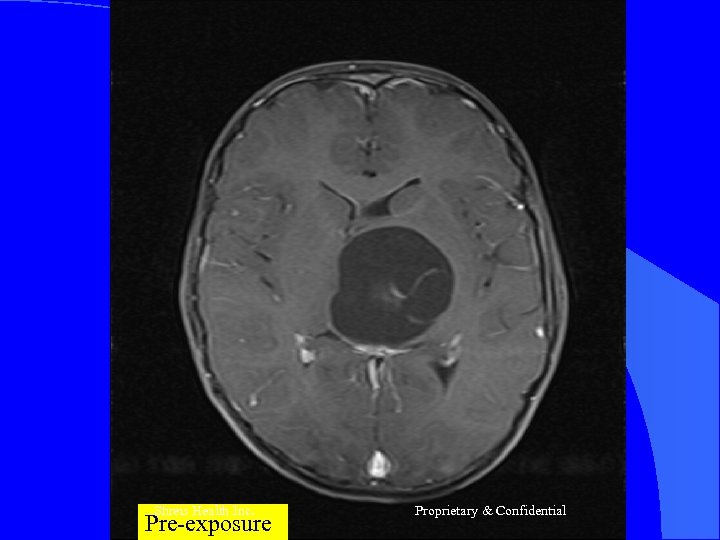

CASE 2 Mr R, 56 yrs l Nov 2004 – MRI Brain = Left frontal SOL (4 x 3 cm) - SX = Craniotomy x decompression of insular glioma HPR = Glioblastoma Grade IV l RT – 60 Gy/30 # till Jan 2005 l CT – Temedol x 2 # till Feb 2005 l Shreis Health Inc. Proprietary & Confidential

l l Presented Feb 05 - Loss of memory - Apathetic - Hemiparesis ® (power 3/5) Today after 1 course of RFQMR - No focal/Gen Neuro deficit - Normal higher functions and back to work. Shreis Health Inc. Proprietary & Confidential

Shreis Health Pre-exposure Inc. Proprietary & Confidential

Shreis Pre-exposure. Health Inc. Proprietary & Confidential